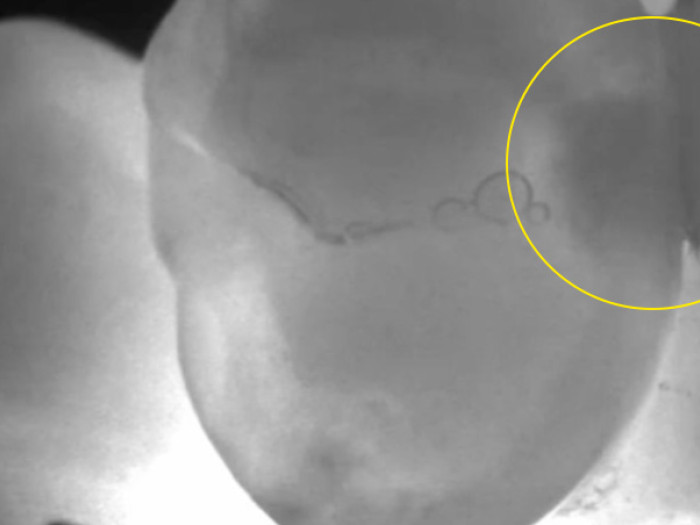

Die dritte Funktion der Kamera ist die Fluoreszenzbildgebung. Die Bakterien, die Fäulnis verursachen, erzeugen ein Stoffwechselprodukt, das bei bestimmten Wellenlängen des Lichts leuchtet (fluoresziert). Die DIAGNOcam Vision Full HD verfügt über LEDs, die diese Wellenlängen emittieren.

Das von dieser Wellenlänge erzeugte Bild lässt den gesunden Zahnschmelz hellgrün erscheinen, ähnlich wie die Schale eines grünen Apfels. Bereiche mit aktiver Karies leuchten rot, so dass sie schnell erkannt werden können.

Einfach ausgedrückt: Wenn es keine Stoffwechselnebenprodukte gibt, gibt es auch keine aktiven kariogenen Bakterien. Auf diese Weise können Ärzte Karies bereits im Frühstadium erkennen und behandeln, und Ärzte, die eine Remineralisierungstherapie anwenden, können sie aktiv überwachen. Der Vergleich von Bildern, die im Laufe der Zeit aufgenommen wurden, kann einen viel besseren Hinweis darauf geben, ob die Läsionen fortschreiten oder schrumpfen.

Wenn Läsionen in einem kleinen Stadium entdeckt werden, können Restaurationen klein und möglicherweise ohne Betäubung durchgeführt werden, wobei die Zahnstruktur erhalten bleibt. Die frühzeitige Erkennung von aktiver Karies trägt auch dazu bei, das Anbringen einer Versiegelung über einem Bereich mit aktiver Karies zu verhindern.

Die Kamera kann auch während restaurativer Verfahren eingesetzt werden, um sicherzustellen, dass alle aktiven Kariesstellen vor dem Einsetzen der endgültigen Restauration entfernt werden.